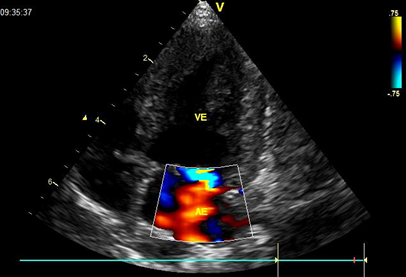

During auscultation, the dog had a heart rate of 141 beats per minute (normal values = 60-160 beats/minute). The Doppler echocardiogram and color flow mapping showed the presence of moderate mitral valve insufficiency (Figure 4).

Figure 4 Doppler echocardiography. Left atrioventricular valve with a thickened appearance of its cusps. The Doppler study and color flow mapping show moderate degree of mitral insufficiency.

Bradycardia is a common finding in dogs with hypothyroidism, since thyroid hormones exert inotropic and chronotropic effects on the heart.17 However, bradycardia was not detected in the dog in this case report. Abnormalities found on the electrocardiogram of dogs with hypothyroidism include sinus bradycardia, weak apical beat, low QRS voltage, and inverted T waves.18 Dogs with hyperadrenocorticism present systemic arterial hypertension, thickening of the interventricular septum and concentric hypertrophy of the left ventricle with development of left heart failure.19–21 However, in the dog under study, only Doppler echocardiogram was performed, and only moderate mitral insufficiency observed.